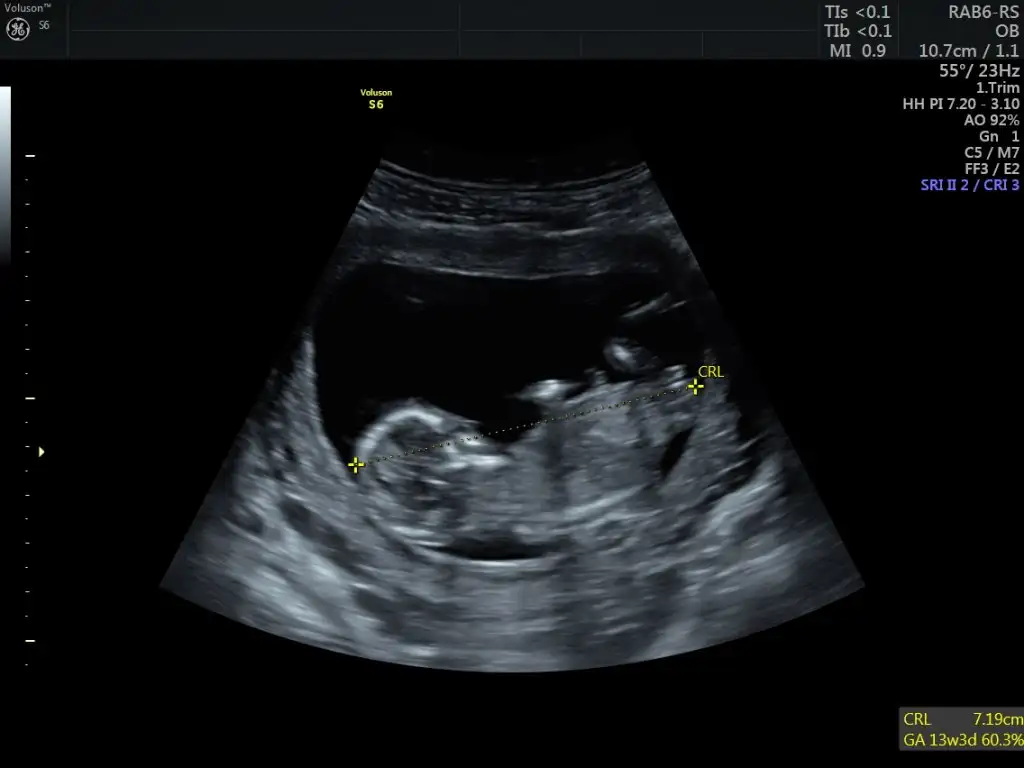

Benim ultrason yarın bana erkek demiştiniz bakalım ne çıkacak

Bildiniz benim oğlum olacakmışMerhaba arkadaşımın kız olacakmış bildiniz.